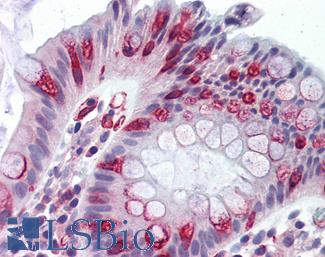

Anti-KRT20 / Cytokeratin 20 antibody IHC of human small intestine. Immunohistochemistry of formalin-fixed, paraffin-embedded tissue after heat-induced antigen retrieval. Antibody LS-B5959 dilution 1:50. This image was taken for the unconjugated form of this product. Other forms have not been tested.

CK7 (KRT7)